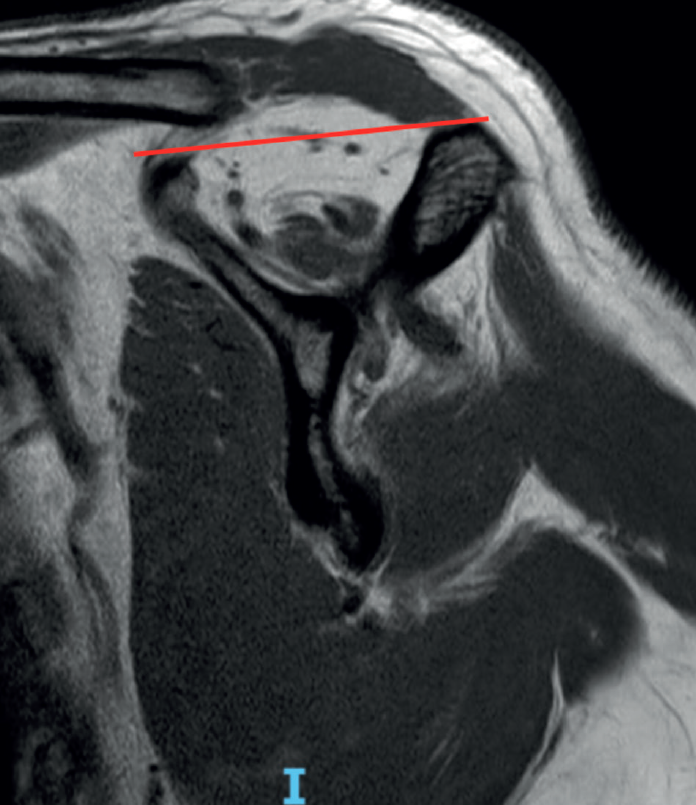

The fish backbone sign(18), in which the muscle belly presents a veined or streaky pattern reminiscent of a fish backbone, is another indicator of fatty infiltration of the muscle belly in the axial axis of the CAT scan, and is equivalent to Goutallier grade 3. The classification of Goutallier has been validated in MRI, and measurement is made in the sagittal section where the scapular spine comes into contact with the body of the scapula, producing a "Y" shaped image(19). Another predictor of irreparability and also an indicator of advanced fatty infiltration is the tangent sign of Zanetti et al.(20). According to the authors, advanced fatty infiltration is present when on tracing a line from the upper margin of the coracoid process to the upper margin of the scapular spine in the same sagittal section of an MRI scan in which a "Y" image is obtained, there is no cut in the muscle volume of the supraspinatus (Figure 3). When measuring in the sagittal view of an MRI scan, we must take into account that a healthy muscle presenting some retraction may simulate greater than real fatty infiltration, and conversely, the muscle may seem normal postoperatively, suggesting that the fatty infiltration has reverted, when in fact it is only healthy but retracted muscle. Fatty infiltration is irreversible and progressive, and although minor improvements have been observed after the repair of these tendons(21), the results are generally poorer than in situations of low grades of adipose atrophy, especially of the infraspinatus(22). Thus, one of the aims of early repair (within 2.5 years from symptoms onset) of rotator cuff injuries is to prevent the condition from progressing to higher grades of adipose atrophy associated with irreversible loss of function and the concept to irreparability(23).